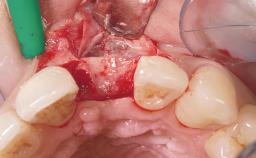

A 30-year-old female patient was referred to the office for the treatment of tooth 11. Her chief concern at the initial visit was to inquire, “Why is my tooth pink?” Upon clinical examination, it was determined that tooth 11 had a previous history of trauma and that the clinical crown had become noticeably pink in color as a result of internal resorption. This diagnosis was confirmed radiographically, indicating a large radiolucency involving the central and distal portions of the clinical crown. It was determined that restoration of this tooth was not possible, and that extraction was indicated. The presence of a mid-line diastema, which the patient wanted to reproduce, directed the treatment plan for tooth replacement utilizing a dental implant.